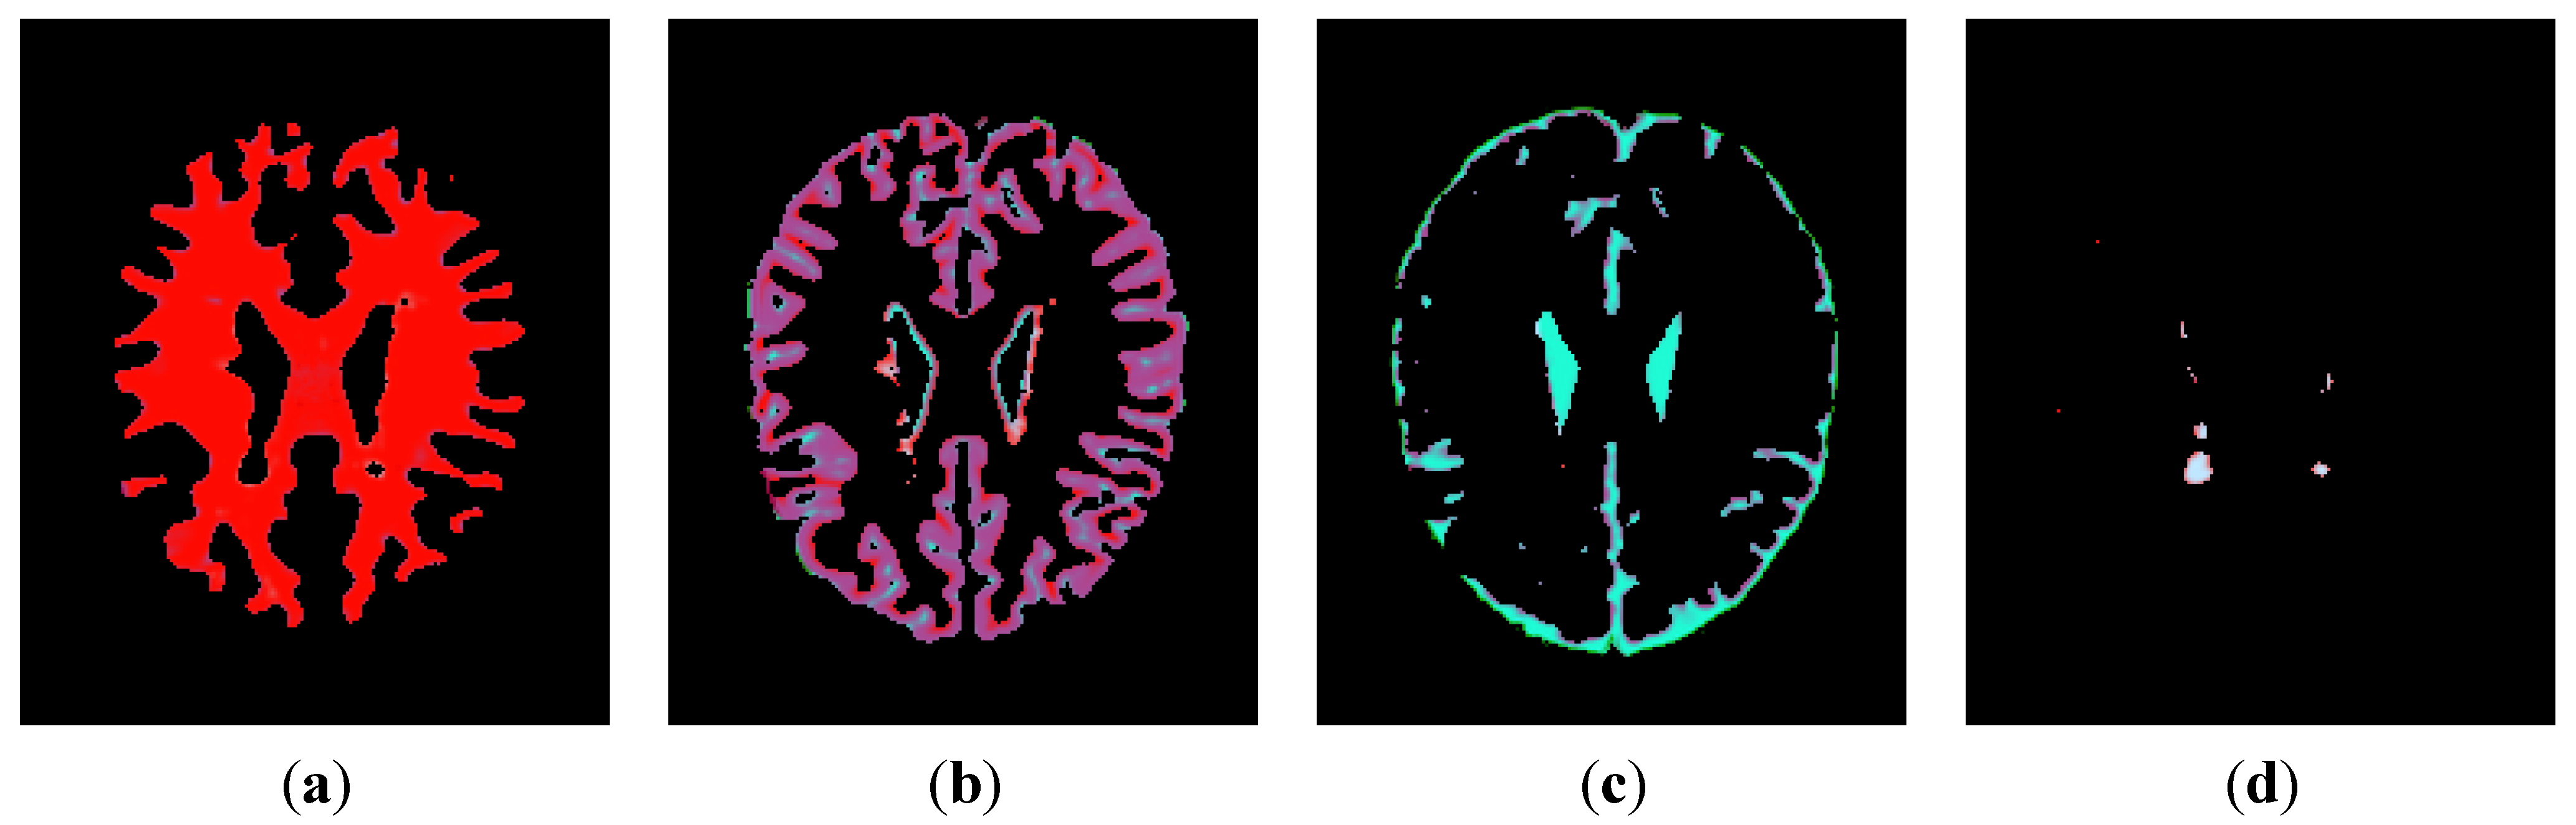

3.1.1. Estimation of Pseudo-Color Tissue Intensity Averages via IJM Image Segmentation

3.1.2. Contrast Equalization via a Pseudo-Grayscale Conversion